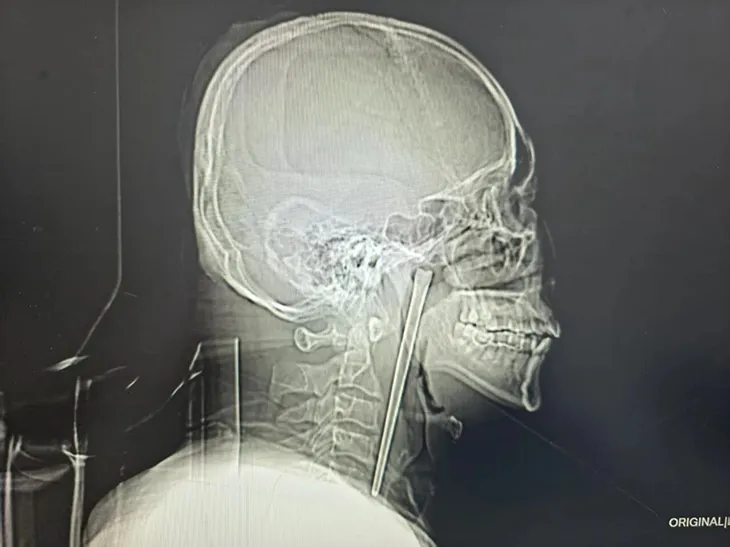

Ảnh chụp X-quang chiếc đũa dài khoảng 12 cm nằm trong cổ họng bệnh nhân. Ảnh: YouTube

Một người đàn ông Trung Quốc đã sống suốt 8 năm với một chiếc đũa kim loại mắc trong cổ họng trước khi được phẫu thuật lấy ra thành công. Theo báo cáo bệnh án được công bố gần đây, bệnh nhân, được xác định là ông Wang, 46 tuổi, đã vô tình nuốt phải một chiếc đũa kim loại dài khoảng 12 cm trong bữa ăn vào năm 2018 khi đang trong tình trạng say rượu. Sau sự cố, ông đã đến cơ sở y tế kiểm tra nhưng từ chối phẫu thuật do lo ngại phải mổ mở vùng cổ.